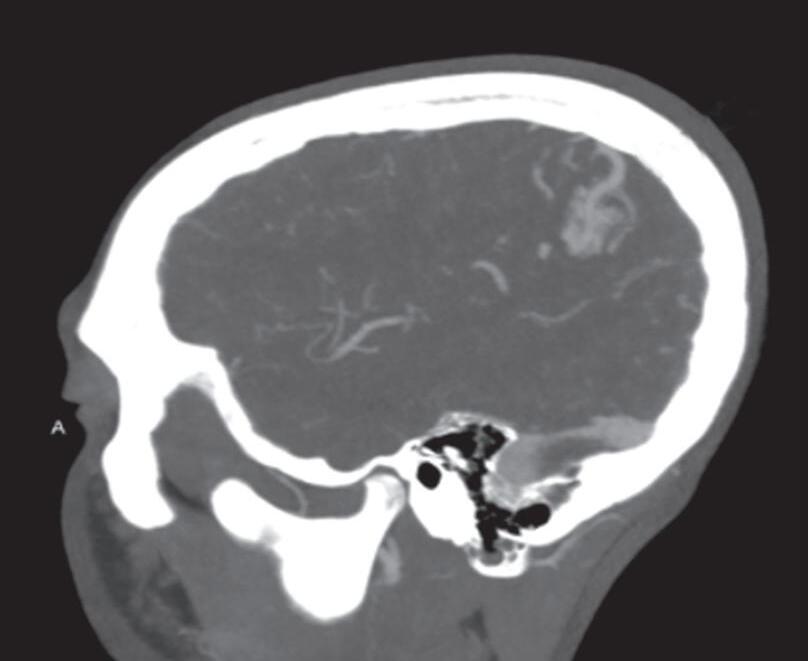

A suspeita diagnóstica das MAVs geralmente é feita por meio de métodos não invasivos de aquisição de imagem, tais como tomografia computadorizada (TC), angiotomografia, ressonância magnética (RNM) e angiorressonância, contudo, as informações anatômicas vasculares necessárias para o planejamento e a execução terapêutica demandam geralmente do estudo dinâmico da angioarquitetura da MAV pela arteriografia cerebral, considerado o exame padrão-ouro para o diagnóstico (Figs. 1-21 e 1-22).35

Em virtude de as manifestações clínicas não serem exclusivas das MAVs, a tomografia computadorizada do crânio sem contraste

é geralmente o primeiro exame realizado na investigação diagnóstica. Algumas alterações presentes nessa tomografia, associadas à história clínica do paciente podem direcionar a suspeição diagnóstica; são eles: pacientes jovens com hemorragia intraparenquimatosa lobar espontânea, sangramento inexplicável intraventricular ou subaracnóideo, presença de calcificações curvilíneas ou salpicadas, ou imagens serpiginosas espontaneamente hiperdensas, que podem corresponder a vasos anômalos integrantes do nidus, a veias de drenagem ou a artérias nutridoras dilatadas. Embora a angiotomografia possibilite uma melhor visualização das estruturas vasculares, a ressonância magnética em contrapartida, permite melhor

visualização da anatomia cerebral, das alterações parenquimatosas, bem como: gliose peri ou intranidal, atrofia parenquimatosa com dilatação focal do sistema ventricular, possibilita a diferenciação da hemorragia aguda da crônica (visualização da hemossiderina nas sequências gradiente eco [GRE] e hidrocefalia (secundária a hemorragia prévia e ou compressão do sistema ventricular por veias de drenagem dilatadas).35